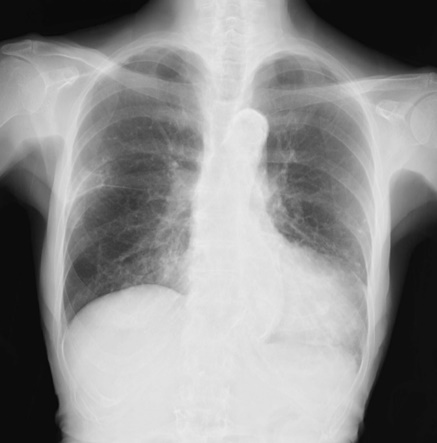

胸部単純X線

37.8℃の発熱あり。呼吸数18回/分、血圧134/60mmHg, 脈拍90/分、SpO2 94%